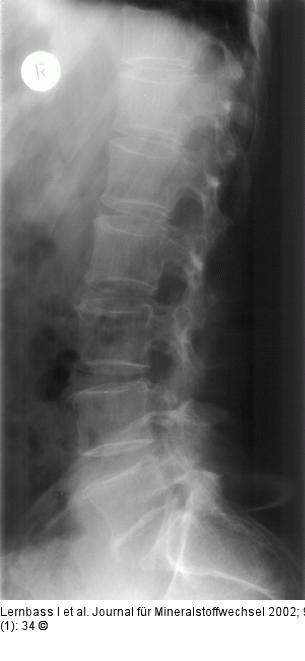

Abbildung 2: Osteoporose - Wirbelsäule Verminderte Röntgendichte und Rarefizierung der trabekulären Binnenstrukturen sämtlicher Wirbelkörper im Sinne einer optischen Säulenbildung. |

Abbildung 2: Osteoporose - Wirbelsäule

Verminderte Röntgendichte und Rarefizierung der trabekulären Binnenstrukturen sämtlicher Wirbelkörper im Sinne einer optischen Säulenbildung. |